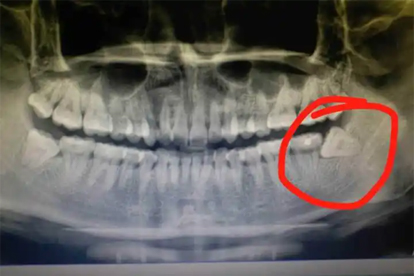

建议每年进行一次口腔检查,通过X光片评估智齿生长状态。日常出现牙龈肿痛、咀嚼不适或口腔异味时,应及时就诊。拔牙后24小时内避免漱口或进食过热食物,按医嘱使用抗生素如阿莫西林胶囊预防感染。保持口腔卫生,选择软毛牙刷清洁创口周围,有助于减少术后感染风险。